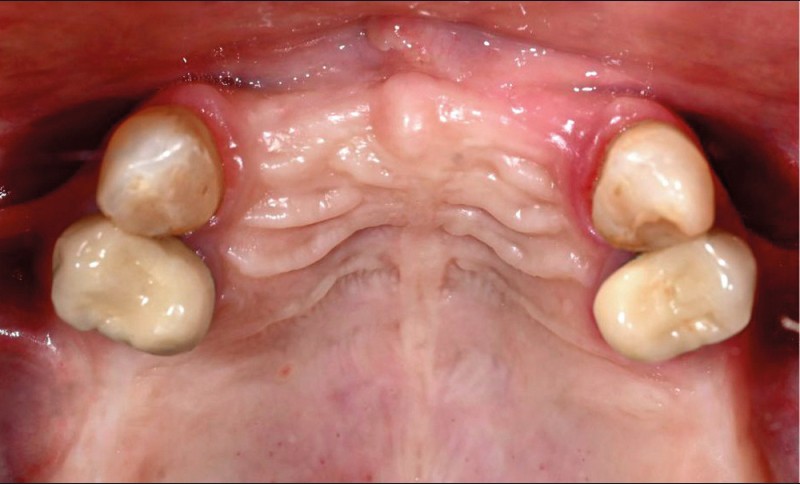

Le matching classique avec les fichiers STL et Dicom fut imprécis. La technique inspirée du « double scan » à l’aide de points radio-opaques sur la PAP provisoire maxillaire et d’un double CBCT a permis d’obtenir un matching extrêmement précis et la conception d’un projet prothétique numérique (Nemotec) associé à un Smile design (fig. 2). La modélisation 3D et le CBCT ont permis d’élaborer une planification implantaire, des guides à étages et un bridge complet provisoire en PMMA usiné (Biotech). La planification de 8 implants au niveau des 7/6/4/3 en fonction du volume osseux disponible et du projet prothétique virtuel a confirmé la possibilité de proposer un traitement sans greffe antérieure (fig. 3).